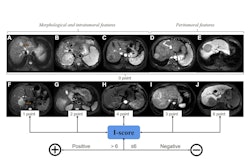

A diffusion-weighted imaging (DWI) MRI technique that corrects for fat in the liver appears to perform comparably to MR enterography (MRE) for detecting liver scarring (i.e., fibrosis) in patients with metabolic dysfunction-associated steatotic liver disease (MASLD), researchers have reported.

"Fit-based non-Gaussian DWI with fat correction could potentially be used with similar diagnostic accuracy as MRE for detecting fibrosis in patients with MASLD," wrote a team led by doctoral candidate Omaïma Saïd of the Université Paris Cité in France. The findings were published October 24 in the Journal of Magnetic Resonance Imaging.

Fibrosis is an important predictor of long-term survival in MASLD patients, and DWI measures molecular diffusion of water in tissues and "changes in tissue microstructure can lead to variations in the apparent diffusion coefficient," the group explained. Measuring these variations can help stage liver fibrosis treatment, but compared with MRE -- and even though it is simpler to acquire -- conventional DWI has shown only middling accuracy for staging liver fibrosis.

Non-Gaussian DWI has been proposed for the diagnosis of liver fibrosis, but its effectiveness can be hindered by the presence of fat in the liver, the investigators wrote. (A non-Gaussian approach better identifies features such as cellularity and tissue heterogeneity, they noted.) The team conducted a study that explored whether a fat-corrected MRI protocol could improve the assessment of fibrosis in this patient population.

The research consisted of data from 222 individuals with type 2 diabetes, hepatic steatosis, and elevated aminotransferases from between October 2018 and June 2021. All study participants underwent liver biopsy and MRI. MR imaging was performed on a 3-tesla system and included DWI using spin-echo echo-planar imaging, MRE using gradient echo sequence, and fat fraction imaging using a multiple gradient echoes sequence. The group estimated diffusion coefficients using two non-Gaussian models: a shifted apparent diffusion coefficient (sADC) and a nonlinear least squares fit (ngADC) -- both of which were calculated with and without intravoxel fat correction using proton density fat fraction (PDFF).

Overall, the researchers reported that the DWI technique performed comparably to MRE when it came to discriminating fibrosis stage F0 versus F1 to F4 for ngADC (corrected for fat) and stiffness, with AUCs of 0.66 and 0.68, respectively (p < 0.05). (Fibrosis stages range from 0 to 4, with 0 indicating no fibrosis and 4 indicating cirrhosis).

"[Our] findings suggest that fat-corrected MRI may help doctors detect liver fibrosis more reliably in patients with fatty liver disease," Saïd and colleagues concluded.